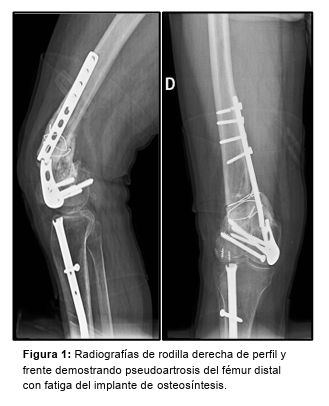

Paciente de sexo masculino, de 49 años, consulta por mínimas molestias en su rodilla derecha de 3 meses de evolución tras caída de 2,5 metros de altura trabajando como albañil. Antecedente a los 29 años de artrodesis tibiotalar y a los 44 años de osteosíntesis de fémur distal derecho con placa por medial y clavo endomedular de tibia ipsilateral. En las radiografías se observa pseudoartrosis con ruptura de la placa femoral y deseje en valgo del fragmento distal (Figura 1). Se encuentra además, una fístula sobre el tornillo de bloqueo distal del clavo de tibia. Se solicitan parámetros inflamatorios (VSG: 58 mm/1*hora, PCR: 4,65 mg/dl), escanograma y se indica descarga axial con el uso de muletas.